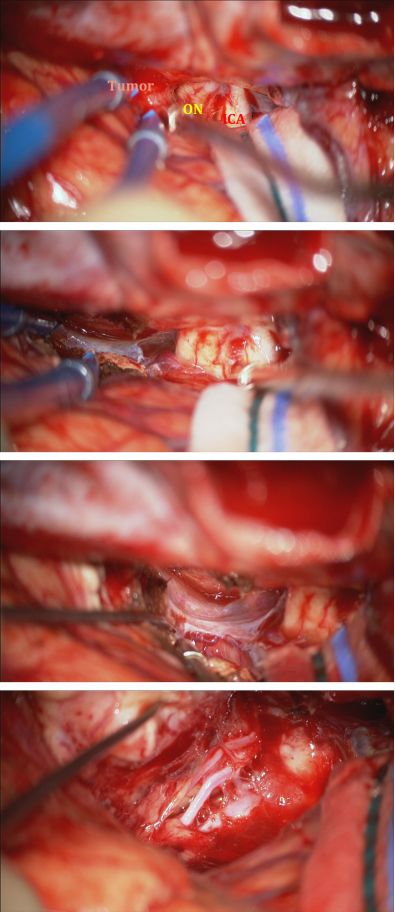

图16. 图为经右侧翼点入路的术中示意图。第一张图展示了肿瘤后极与周围神经血管结构的关系。额下外侧途径早期即可以辨认出肿瘤与其周围的视神经和颈内动脉。在保护视神经和颈内动脉的同时,对肿瘤基底切断血供(第二排)。肿瘤基底部血供被完全切断,直至对侧眶壁及对侧额下区的软膜完全暴露(第三排)。在肿瘤瘤内减压并分块切除后,将大脑前动脉及其分支从肿瘤后极上游离。